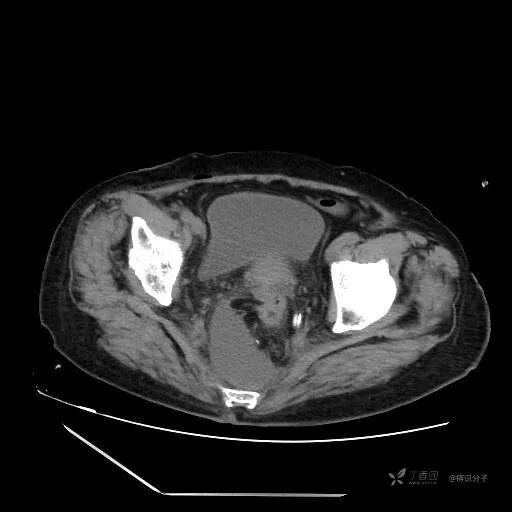

辅助检查:查腹部 CT 示骶前包裹性积液,距离引流管较远,吻合口周围未见明显渗出和气体征象。